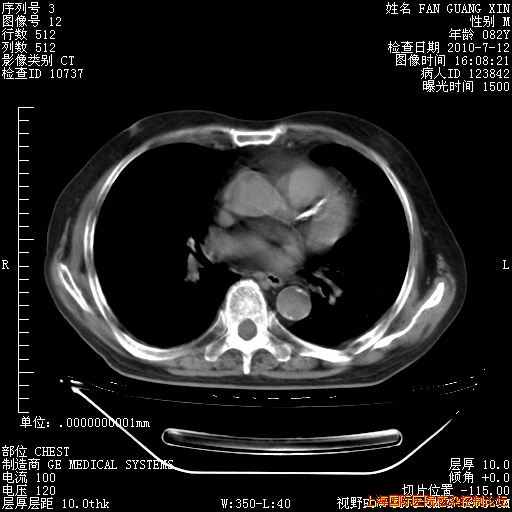

今天CT

整整相隔30天的肺部CT好像有所好转啊。甲强龙减量第3天,需要观察体温。

海管,自昨日你和我通完话后,不知您岳父消化道症状有无缓解?体温怎样?阅读7.12日胸部ct,个人认为目前激素治疗是有效的,甲强龙减量是适宜的。因在抗痨治疗,需密切观察肝功、肾功能和血常规。不过,老年、长期住院和大量使用激素,很担心菌群失调发生